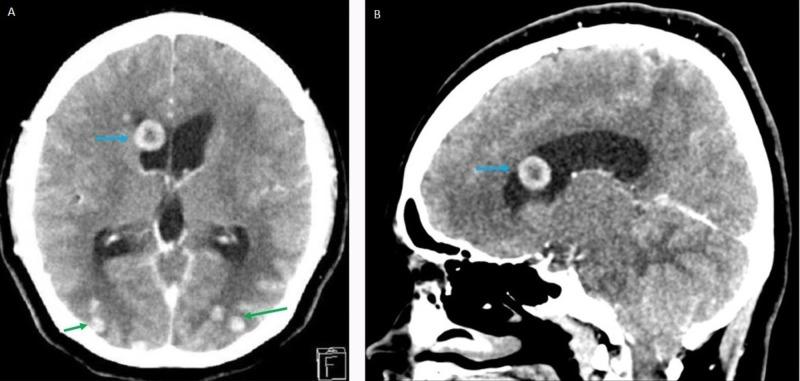

Intracranial tuberculoma is a rare manifestation of tuberculosis involving the central nervous system. The involvement of the ventricular system is extremely uncommon. We describe a young woman with bilateral papilledema secondary to intraventricular tuberculoma with hydrocephalus. She was treated with anti-tuberculosis therapy and intravenous dexamethasone. Her visual acuity deteriorated after one month of treatment. We provide a literature review of this uncommon ocular sequelae.

颅内结核瘤是结核病累及中枢神经系统的一种罕见表现。脑室系统受累极为罕见。我们描述了一名年轻女性,她因脑室结核瘤伴脑积水继发双侧视乳头水肿。她接受了抗结核治疗和静脉注射地塞米松。治疗一个月后她的视力恶化。我们对这种罕见的眼部后遗症进行了文献综述。